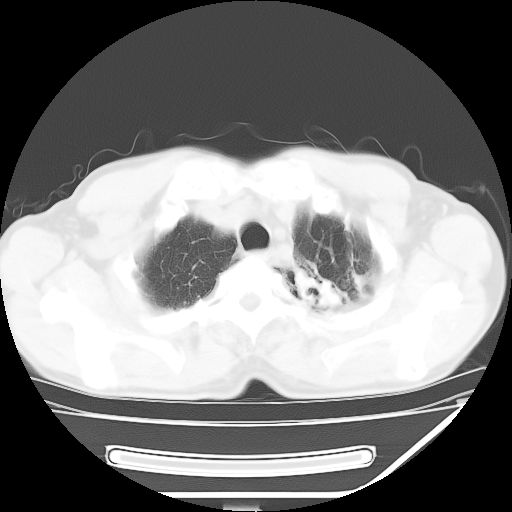

男,59岁,“结核性胸膜炎”30余年,胸部经常疼痛,多次x检查提示“肺部”炎症。腹部疼痛5日,b超提示:“肝内短管结石,余显示不清,建议进一步检查。”

两肺结核并右侧胸腔积液;脾脏、腹腔及腹膜后淋巴结结核[陈旧性];肝内胆管结石

胸部腹部都是结核(双肺。纵隔淋巴结,肝脏,脾脏,肠系膜)